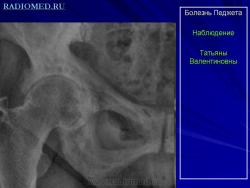

Болезнь Педжета проявляется у больных в возрасте старше 40 лет. Заболеваемость варьирует в пределах 0,1–3% населения. У лиц моложе 40 лет частота заболеваемости не превышает 0,5%, у лиц старше 90 лет частота заболеваемости около 10%. Деформирующий остоз чаще встречается у мужчин. Поражение только одной кости (монооссальная форма), преимущественно большеберцовой, бедренной, или таза встречается редко, в 85% в процесс вовлекается множество костей (длинные кости, кости таза, черепа и позвоночника) ― полиоссальная форма. В основном поражаются кости, несущие наибольшую механическую нагрузку (поясничные и крестцовые позвонки, бедренная и большеберцовые кости и др.); характерны поражения костей крыши черепа; из лицевых костей чаще поражаются челюсти.

Деформирующая остеодистрофия (болезнь Педжета) чаще проявляется у мужчин в возрасте 40-60 лет, характеризуется постепенно прогрессирующим утолщением коркового слоя костей с развитием гиперостозов, деформацией, искривлением костей, беспорядочностью их структуры, образованием в них кист; поражаются кости мозгового черепа, позвоночника и длинных трубча­тых костей. Размеры мозгового черепа увеличиваются, наружная пластинка костей свода черепа местами утолщена, гиперостозы чередуются с участка­ми беспорядочного разрежения кости. В связи с деформацией костных от­верстий и каналов основания черепа и межпозвонковых отверстий наруша­ется функция черепных и спинномозговых нервов, возможны расстройства кровообращения. Деформация глазниц обусловливает экзофтальм. Нередко отмечаются признаки внутричерепной гипертензии. Позвонки сплющены; в трубчатых костях сужены костномозговые каналы, возможны патологические переломы костей, при этом линия перелома четкая, ровная, как при переломе очищенного банана («банановый перелом»); усилены физиологические изгибы позвоночника. Процесс может быть относительно ограниченным или распро­страненным. Содержание кальция и фосфора в крови нормально или слегка увеличено, активность щелочной фосфатазы повышена. Предполагается доми­нантный тип наследования с различной экспрессивностью. Описал болезнь в 1877 г. английский хирург J. Paget (1814-1899).

В монооссальных случаях, частота которых, согласно публикациям, начинается от 10-20% доходя до почти 50%, дифференциальный диагноз может быть гораздо сложнее. В огромном большинстве случаев БП, наличие неоднородных участков костного склероза или остеолиза с искажением трабекулярной архитектуры в сочетании с кортикальным утолщением и фокальным утолщением кости практически патогномоничен для данного заболевания. Бедренная кость является второй наиболее распространенной монооссальной локализацией после таза. В случаях, когда имеется ее дистальное поражение, рентгенологические признаки, характерные для БП, выявляются с меньшей частотой или менее выражены, так что дифференциация с другими процессами, в частности, опухолевыми, может быть затруднена.